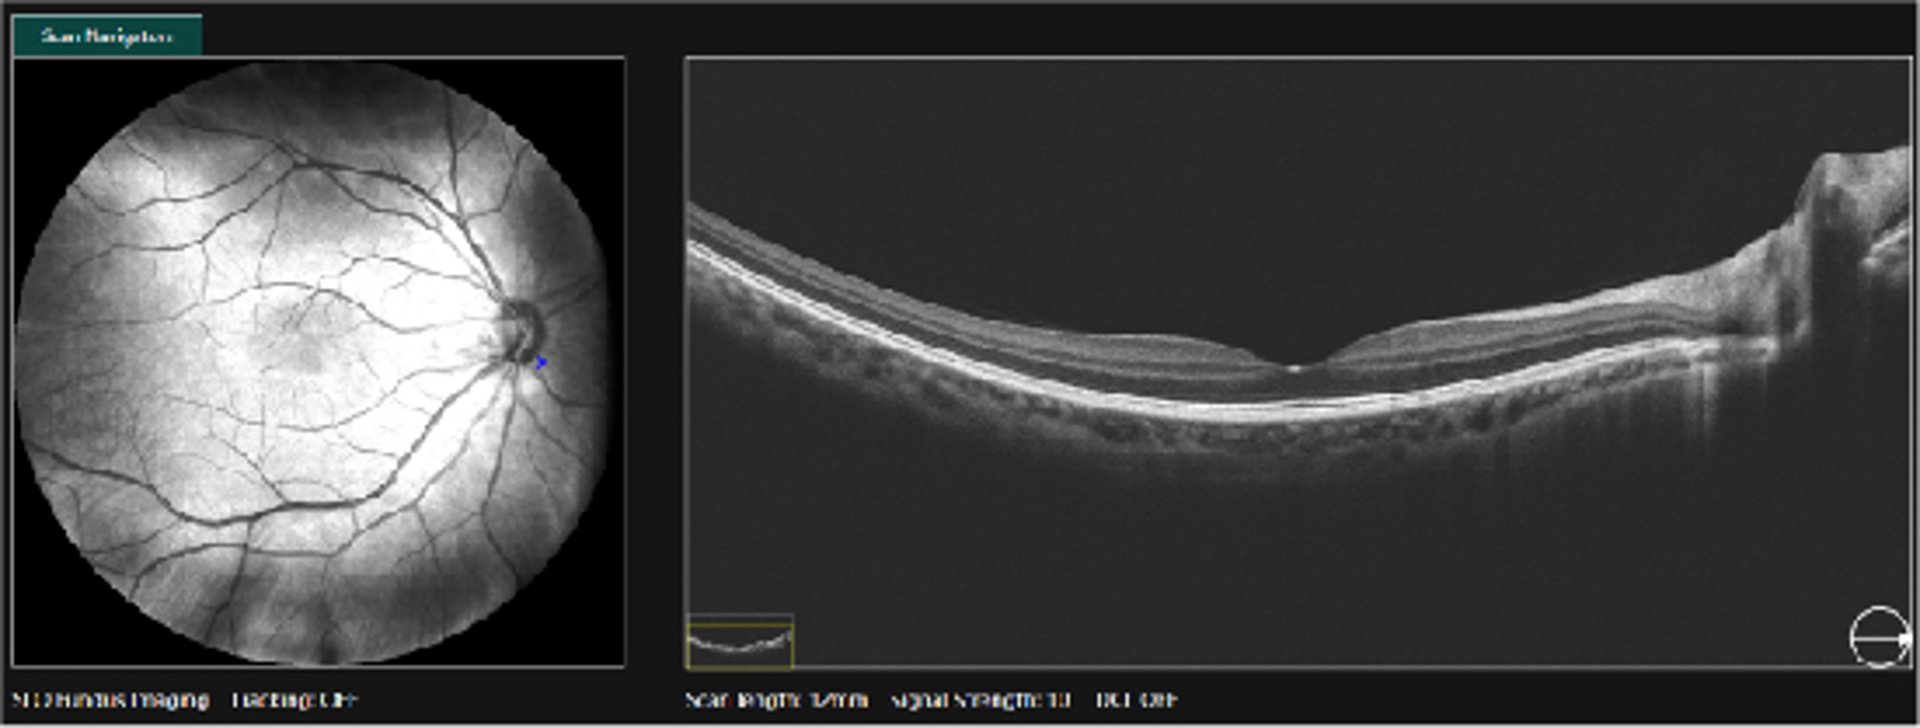

Για την διάγνωση της διαβητικής αμφιβληστροειδοπάθειας κάνουμε λεπτομερή οφθαλμολογικό έλεγχο, που περιλαμβάνει βυθοσκόπηση με οπτική τομογραφία συνοχής (OCT) και φλουοροαγγειογραφία όπου χρειάζεται. Αυτές οι εξετάσεις μας επιτρέπουν να ανακαλύψουμε αλλα και να παρακολουθούμε μετέπειτα τις βλάβες στον αμφιβληστροειδή.